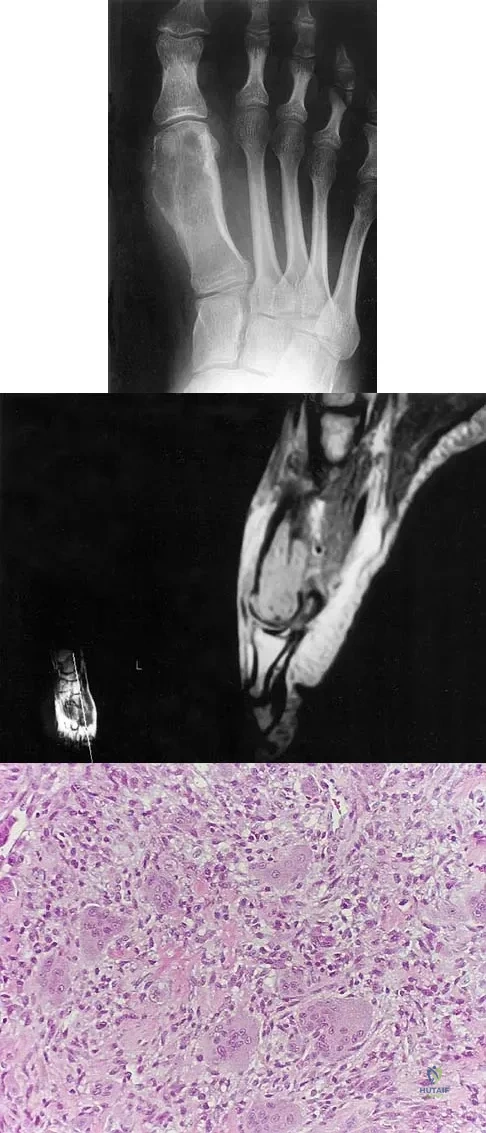

A 16-year-old girl has had anterior leg pain and a mass for the past 8 months. Figures 2a and 2b show a radiograph and an H & E histologic specimen. Which of the following disorders is believed to be a precursor of this lesion?